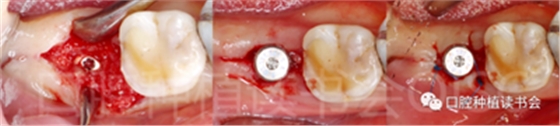

5.3.9 術后第6周,47行種植2期手術,可見種植體周圍愈合良好,牙齦成型后,旋入愈合基臺(圖22)。

圖22 種植體周圍獲得了良好的骨整合。